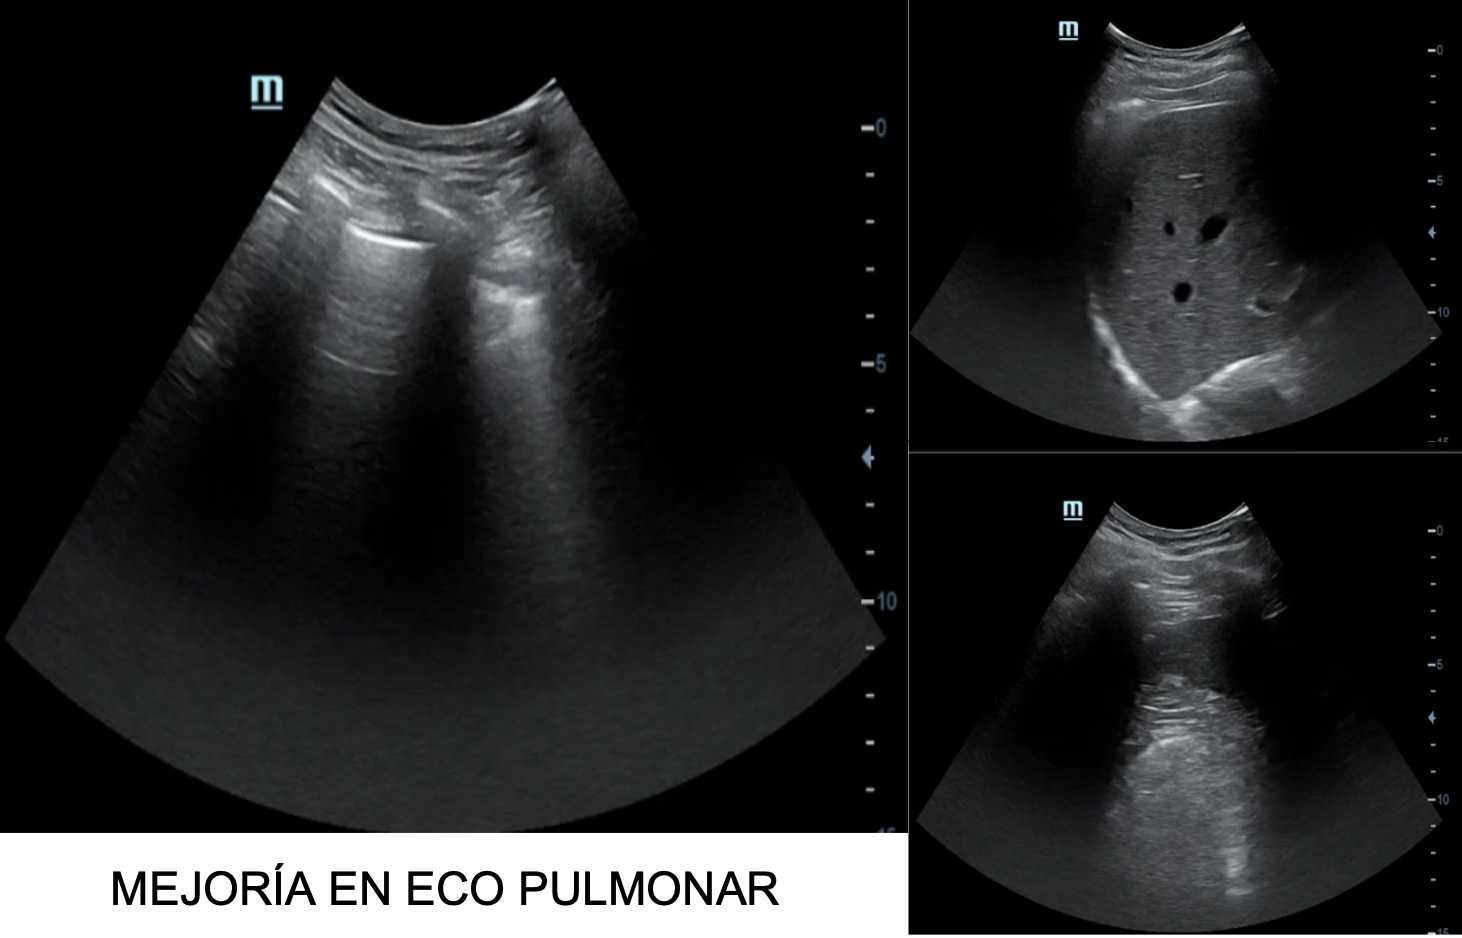

A posteriori en consulta se realiza ecografía de control donde se observa la desaparición de líneas B y resolución del derrame pleural bilateral.

Del mismo modo, nos gustaría subrayar nuestra capacidad de controlar la evolución del paciente en visitas posteriores haciendo uso del ecógrafo.